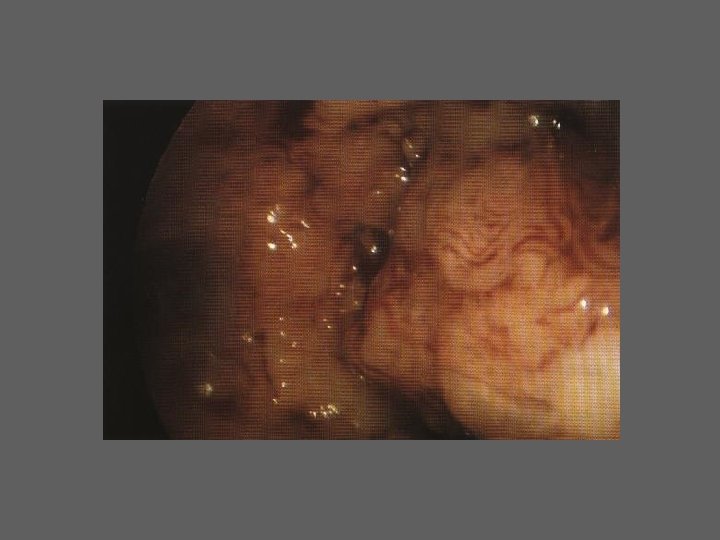

TIPOS DE HISTEROSCOPIA Diagnóstica – Histeroscopia Cirurgica

HISTEROSCOPIA DIAGNÓSTICA • Indicações /Importância (6 grupos) I. Esclarecimento de determinados sintomas ou de situações ginecológicas particulares II. Infertilidade III. Oncologia IV. Antecedentes de complicações Obstétricas específicas V. Esclarecimento de resultados “anormais” de outros meios de diagnóstico VI. Avaliação pré e pós-operatória da cirurgia histeroscópica

HISTEROSCOPIA - INDICAÇÕES Todas a situações em que se julgue vantajosa uma visualização completa da cavidade uterina, em particular: – Metrorragias – Dismenorreia adquirida – Infertilidade – Abortamentos de repetição e parto pré-termo – HSG anormal – DIU “perdido” – GIFT e ZIFT – Tratamento cirúrgico da patologia intracavitária: ● pólipos, miomas, septos, sinéquias, recessões endometriais ● baixos custos, reduzida morbilidade